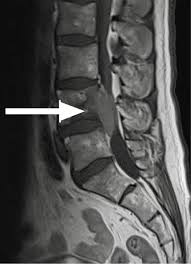

Metastatic Disease Of Spine Pathology Orthobullets

Metastatic Disease Of Spine Pathology Orthobullets from upload.orthobullets.com

Metastatic Spine Tumors

Metastatic Spine Tumors from embed.widencdn.net